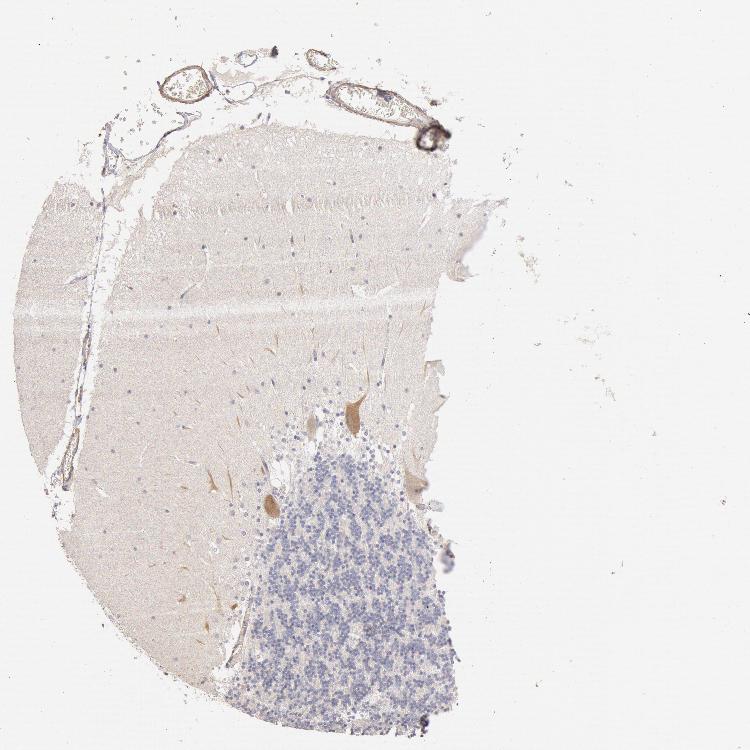

CEREBELLUM - Antibody stainingi

Antibody staining in the annotated cell types in the current human tissue is reported as not detected, low, medium, or high, based on conventional immunohistochemistry profiling in selected tissues. This score is based on the combination of the staining intensity and fraction of stained cells.

Each image is clickable and will lead to virtual microscopy that enables deeper exploration of all samples and also displays staining intensity scores, fraction scores and subcellular localization as well as patient and tissue information for each sample.

Antibody HPA001205

Purkinje cells Medium

Cells in granular layer Not detected

Cells in molecular layer Low